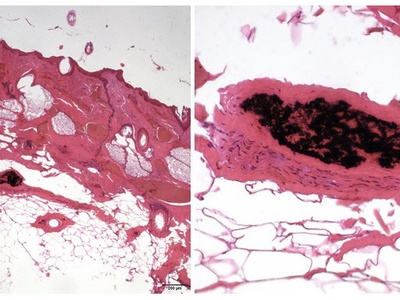

Lymphangitis

Inflammation of lymphatic channels often due to spreading skin infection, marked by red streaks and tender lymph nodes. Signals spreading infection; urgent antibiotic treatment is often needed.

Cellulitis

Diffuse bacterial inflammation of skin and subcutaneous tissue causing redness, warmth, and pain. Can spread rapidly and cause systemic illness; seek care for expanding redness, fever, or rapid progression.